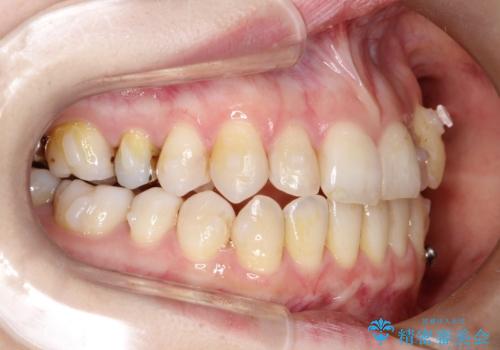

- 左上の八重歯の改善を希望され来院された患者様です。

初診時の歯並びの状態としては、上下ともに前歯部中心としたの中等度のがたつき(叢生)があり、全特に左上の前歯は1本だけ引っ込んでおり、犬歯は外に飛び出した状態でした。

抜歯は行わず上顎の奥のスペースを利用して歯をスライドする方法の他に歯列弓の拡大やディスキング(歯と歯の間の隙間を作る処置)を行い叢生を改善しましています。

歯の大きさの不揃いが原因の正中のズレは、ディスキング量を調整することで合わせました。

矯正装置としてはマウスピースを使用しています。